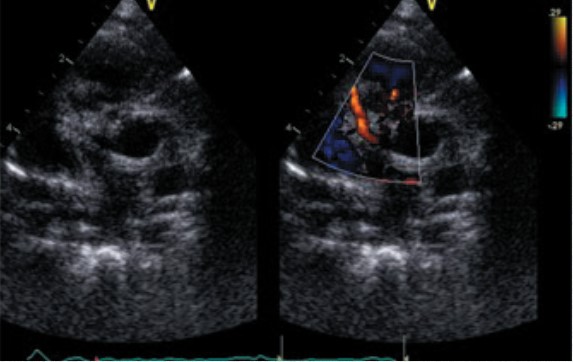

El electrocardiograma demostró ritmo sinusal, frecuencia cardíaca de 150 por minuto, eje a +60, Qtc 0,42 seg. Pr de 0,125 seg. con signos de sobrecarga izquierda (figura 1), la radiografía de tórax mostro discreta cardiomegalia con signos evidentes de hiperflujo pulmonar (figura 2), y el ecocardiograma confirma el diagnóstico de ventana aortopulmonar, la cual mide aproximadamente 5 mm a 11 milímetros del plano valvular aórtico, cavidades izquierdas dilatadas, función sistólica conservada, velo anterior mitral prolapsante con insuficiencia leve a moderada, arco aórtico izquierdo, se descarta ductus y coartación aortica, hipertensión pulmonar severa (figura 3).

Figura 3. Ecocardiograma prequirugico. Eje corto de grandes vasos. Se observa la imagen de la ventana aortopulmonar de 5 mm.

Figura 4. Ecocardiograma postquirúrgico. Eje corto de grandes vasos. Se observa la coronaria derecha normo implantada y llenado en diástole.

Finalmente es dado de alta a los 26 días del ingreso con ecocardiograma donde se observa coronaria derecha normoimplantada (figura 4). Se indica control por consulta externa medicado con captopril, espironolactona y furosemida.